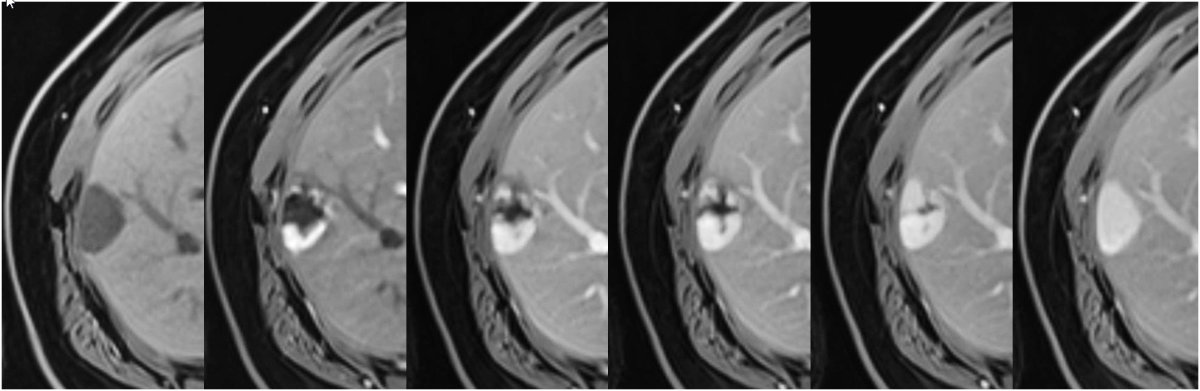

Enhancement characteristics of haemangiomas in MRI (figure 14) are analogous to those on CT. On T2w images, haemangiomas are typically very bright / hyperintense with internal fibrotic areas appearing dark. For patients with incidental liver lesions, multiphase contrast-enhanced CT has a sensitivity of 75.6% to 86.7% (accuracy of 91% to 95%), and MRI has a sensitivity of 86.7% to 97.8% (accuracy of 95% to 99%) for diagnosis of haemangiomas [47].

Figure 14Haemangioma on MRI. Subcapsular haemangioma with hypointense signal on the unenhanced T1w image (left) and after contrast administration peripheral nodular enhancement with filling in over time and hyperintense signal matching the blood pool on delayed phase (right).